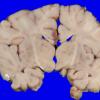

Familial erythrophagic lymphohistiocytosis (4)